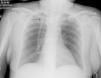

Hemorragia alveolar difusa asociada a púrpura de Schönlein-Henoch e infección por Pneumocistis jirovecci: a propósito de un caso

Diffuse alveolar hemorrhage associated with Henoch-Schönlein purpura and Pneumocystis jirovecii infection: A case report